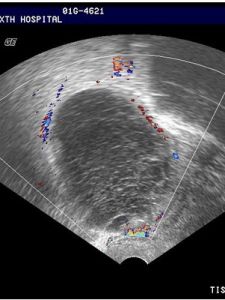

通過不同組織的密度不同,其聲波衰減的程度不一樣,從而反應出正常或異常組織。回聲越高,組織密度越大,低回聲超聲圖像比較暗高回聲超聲圖像比較亮,無回聲的是黑色的,它代表液性的區域,包括血液,膽汁,尿液等。1回聲強弱的描述:根據圖像中不同灰階將回聲信號分為強回聲、等回聲、低回聲和無回聲。而回聲強弱或高低的標準一般以該臟器正常回聲為標準或將病變部位回聲與周圍正常臟器回聲強度的比較來確定。如液體為無回聲,結石氣體或鈣化為強回聲等。正常人體軟組織的內部回聲由強到弱排列如下:腎竇>胎盤>胰腺>肝臟>脾臟>腎皮質>皮下脂肪>腎髓質>腦>靜脈血>膽液和尿液。

高回聲區多為惡性腫瘤、鈣化影、骨骼、金屬環等,低回聲區多為血管瘤、小腫瘤,急性炎症早期水腫,良性瘤或半實性半囊性包塊,局部脂肪堆積。無回聲區內多為液體,多見於膽囊、膀胱、囊腫等液體腔隙,卵巢良性包塊。如果卵巢內的無回聲小暗區,可能為成熟的卵泡,並且有些卵巢內小囊腫(直徑3厘米內)可能是生理性的,定期複查就可以了。在實性腫物內部出現無回聲區代表腫物內部發生液化性壞死。常見的病理性圖像特點

1囊性與實質性病變超聲對液體與實質組織有著顯著的圖像差別,因而很好鑑別。

均質性病變呈均勻一致的低回聲、等回聲或強回聲,非均質性病變則呈複雜的回聲結構。

5良性與惡性病變

一般而言,良性病變質地均勻、界面單一故回聲均勻、規則。惡性病變因生長快,伴出血,變性,瘤內組織界面複雜不均勻,表現為不規則的回聲結構。